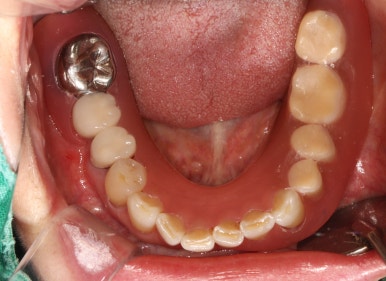

왼쪽 아래 어금니의 임플란트 보철물을 모두 만들고 나서의 임상 사진입니다.

자세히 보시면, 맨 뒤 어금니의 바깥쪽으로 단단하게 보이는 부착치은 (각화치은)이 잘 생착되어 있는 것을 보실 수 있어요!!

비록 많은 양은 아닙니다만,

이 최소한의 2-3mm 폭의 단단한 잇몸은

편하게 양치질을 하게 해주고, 임플란트 주변에 음식물이 끼는 것을 최대한으로 막아준답니다.

그래서 임플란트 주위염의 발생 가능성을 현저히 낮추고, 결과적으로 어금니 임플란트를 오래 쓸 수 있게 해주죠.

치료 완료 후 단단한 잇몸과 볼점막의 경계인 MGJ를 화살표로 표시해 보았는데요,

처음 오셨을 때의 사진을 참고해보시면 이해가 편하실거에요.

아무 치료도 하지 않고 브릿지로 치료가 되어있던 부분은 단단한 잇몸이 하나도 없이 대부분 볼점막의 경계를 갖고 있습니다만,

제가 유리치은이식술을 하면서 지르코니아 임플란트 크라운을 제작해드렸던 부분은

이식해놓은 단단한 잇몸이 아주 깔끔하게 자리잡으며 최적의 컨디션을 보여주고 있습니다.